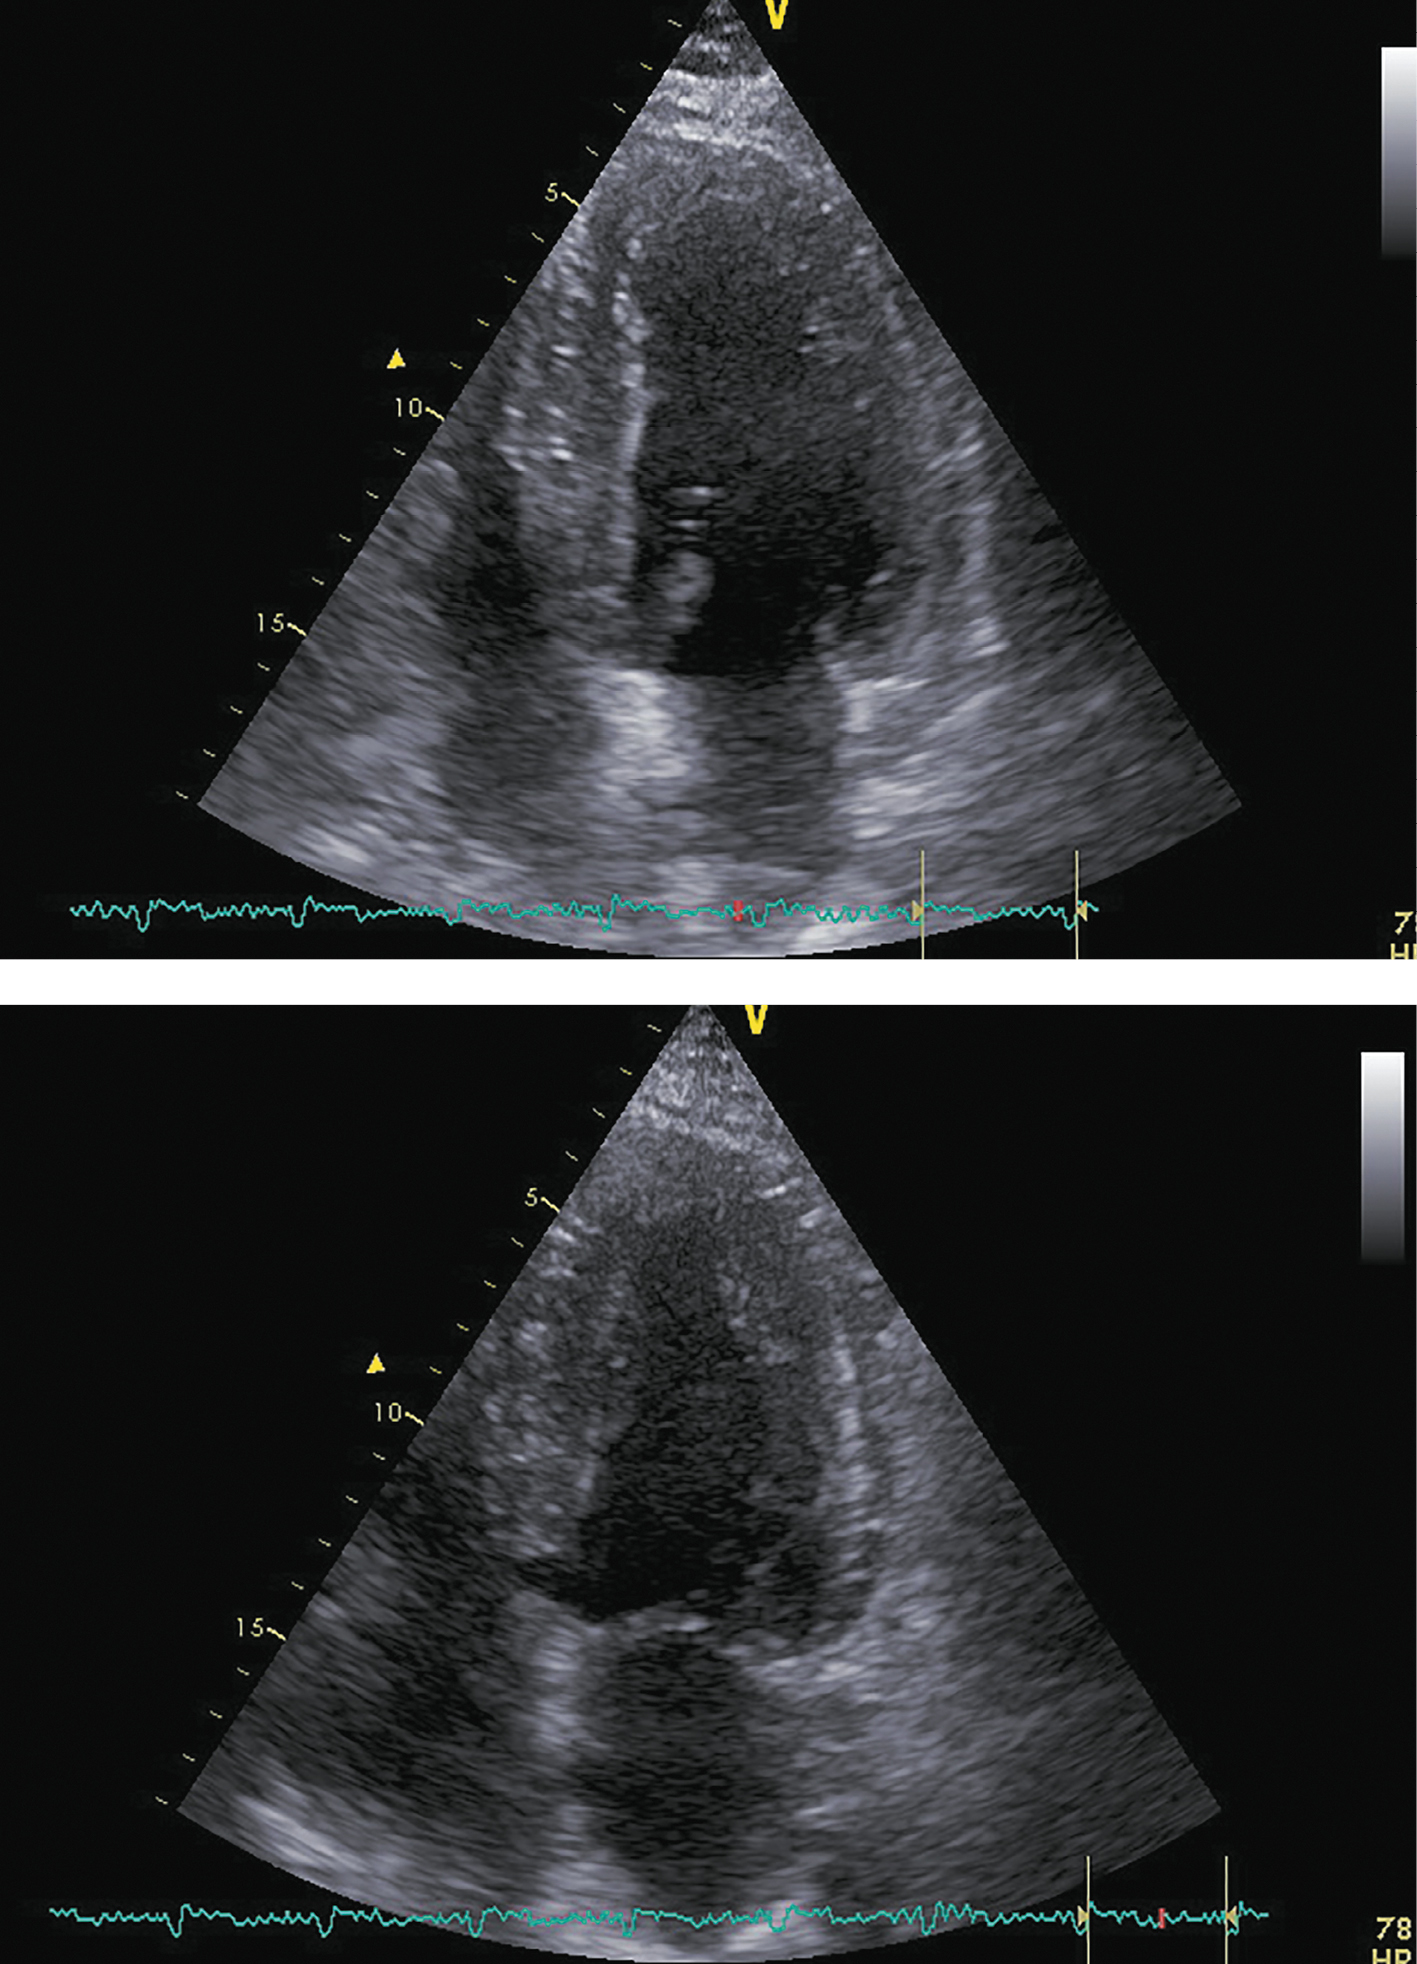

При последующих госпитализациях для динамического наблюдения (май 2018 г.; декабрь 2018 г.; декабрь 2019 г.) состояние пациента соответствовало стабильной клинической ремиссии. Заместительная терапия была отменена в декабре 2018 г., в дальнейшем показатели секреции кортизола находились в пределах референсных значений (табл. 1). Толерантность к физическим нагрузкам оставалась на уровне II ф.к. по NYHA. Физикальная симптоматика, характерная для ХСН, отсутствовала. При проведении контрольных ЭХОКГ-исследований отмечалось дальнейшее уменьшение размеров и объемов левого желудочка со стабилизацией ФВ ЛЖ на субнормальном уровне (рис. 6, 7, 8; табл. 4, 5, 6 соответственно). В связи с сохраняющейся АГ поликомпонентная гипотензивная терапия была продолжена в том же объеме с добавлением к ней альфа-адреноблокатора (доксазозин 2 мг два раза в сутки). СД контролировался метформином с достижением целевого уровня гликемии и гликированного гемоглобина. Уровень креатинина оставался стабильным, значимой динамики СКФ обнаружено не было (табл. 7).

Рисунок 6. ЭХОКГ через 6 месяцев после аденомэктомии.

Примечание: верхушечная 4-камерная позиция (сверху представлен кадр в диастолу, снизу — в систолу).

Рисунок 7. ЭХОКГ через 12 месяцев после аденомэктомии.

Примечание: верхушечная 4-камерная позиция (сверху представлен кадр в диастолу, справа — в систолу.

Рисунок 8. ЭХОКГ через 24 месяца после аденомэктомии.

Примечание: верхушечная 4-камерная позиция (сверху представлен кадр в диастолу, справа — в систолу).

Таблица 4. ЭХОКГ-показатели через 6 месяцев после аденомэктомии

|

Показатель |

Значение/индекс |

Объем левого предсердия |

77 мл/33 мл/м² |

Передне-задний размер левого желудочка |

6,10 см/2,44 см/м² |

Конечно-диастолический объем левого желудочка |

211 мл/91 мл/м² |

Конечно-систолический объем левого желудочка |

103 мл/44 мл/м² |

Локальная кинетика левого желудочка |

Нормальная кинетика |

Фракция выброса левого желудочка (усреднение по 4- и 2-камерным верхушечным позициям) |

51% |

Диастолическая функция левого желудочка |

градация II, псевдо-нормальный тип |

Конечно-диастолическая площадь правого желудочка |

25,5 см²/10,9 см²/м² |

Конечно-систолическая площадь правого желудочка |

14,8 см²/6,4 см/м² |

Фракция систолического уменьшения площади |

41% |

Расчетное систолическое давление в легочной артерии |

41 мм рт.ст. |